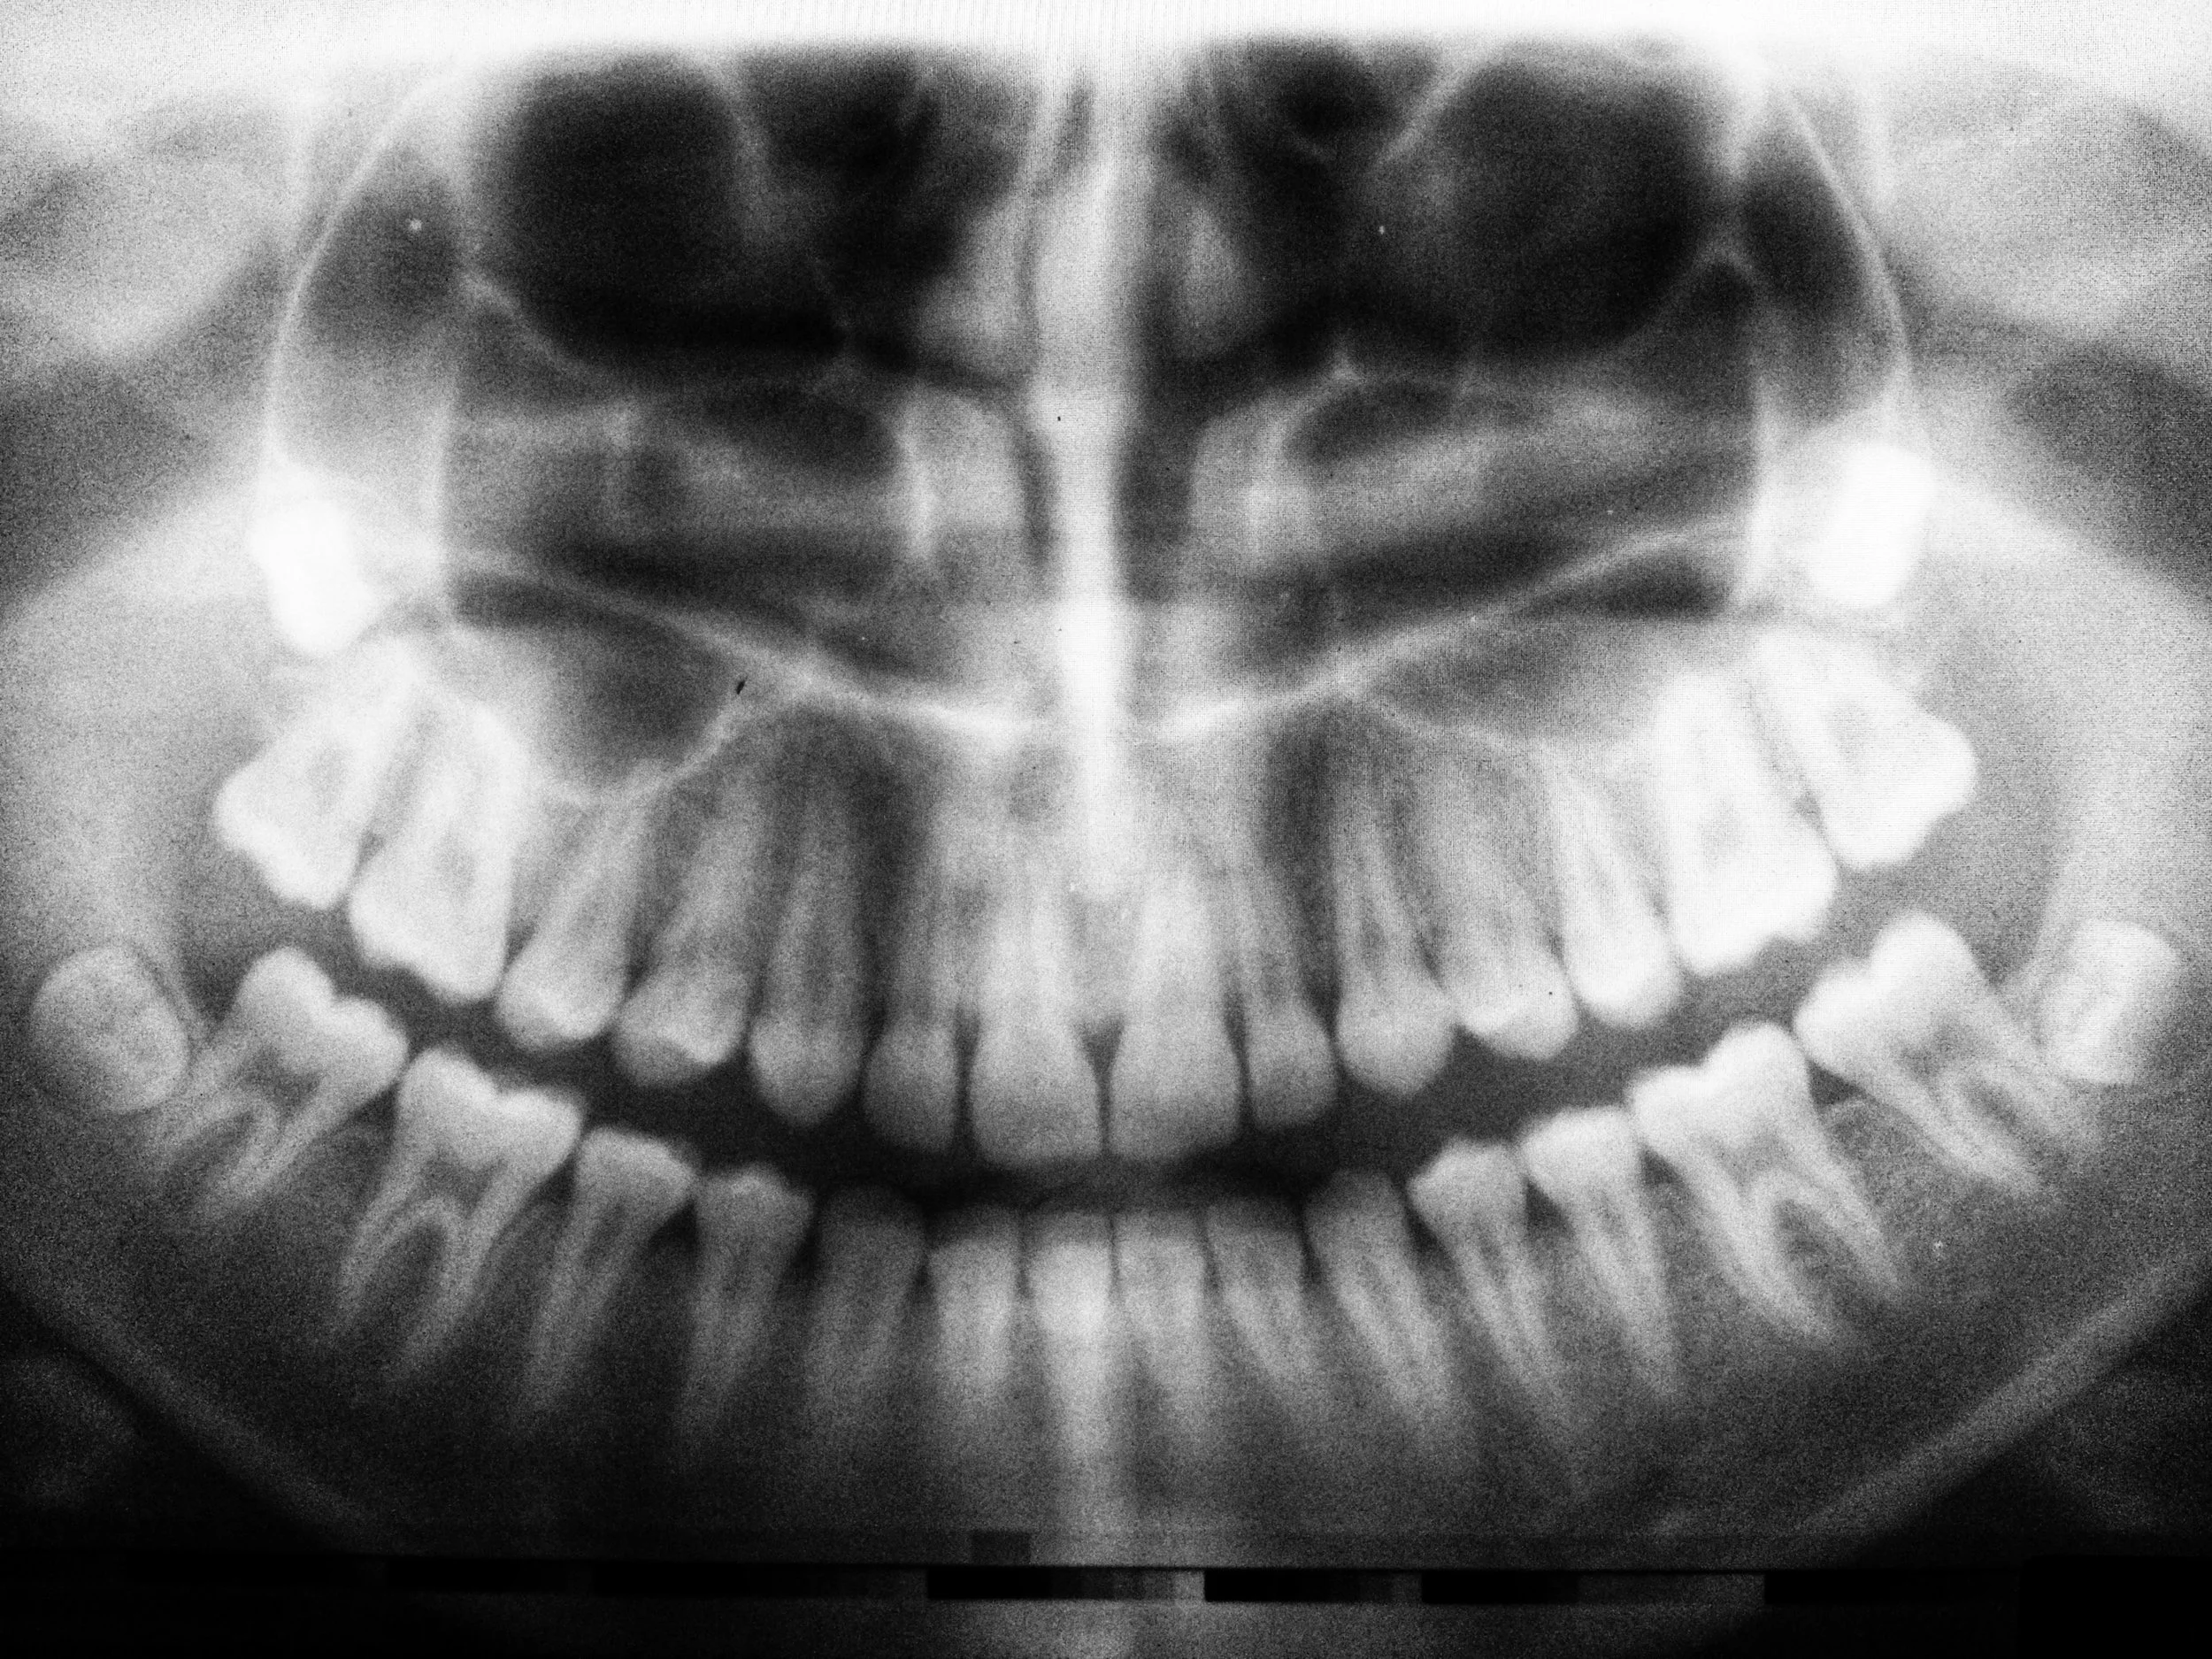

A thorough examination and X-rays by your dentist or oral surgeon can determine whether removal is necessary.

Consultation and Evaluation: An initial exam and X-rays to assess the position of your wisdom teeth.